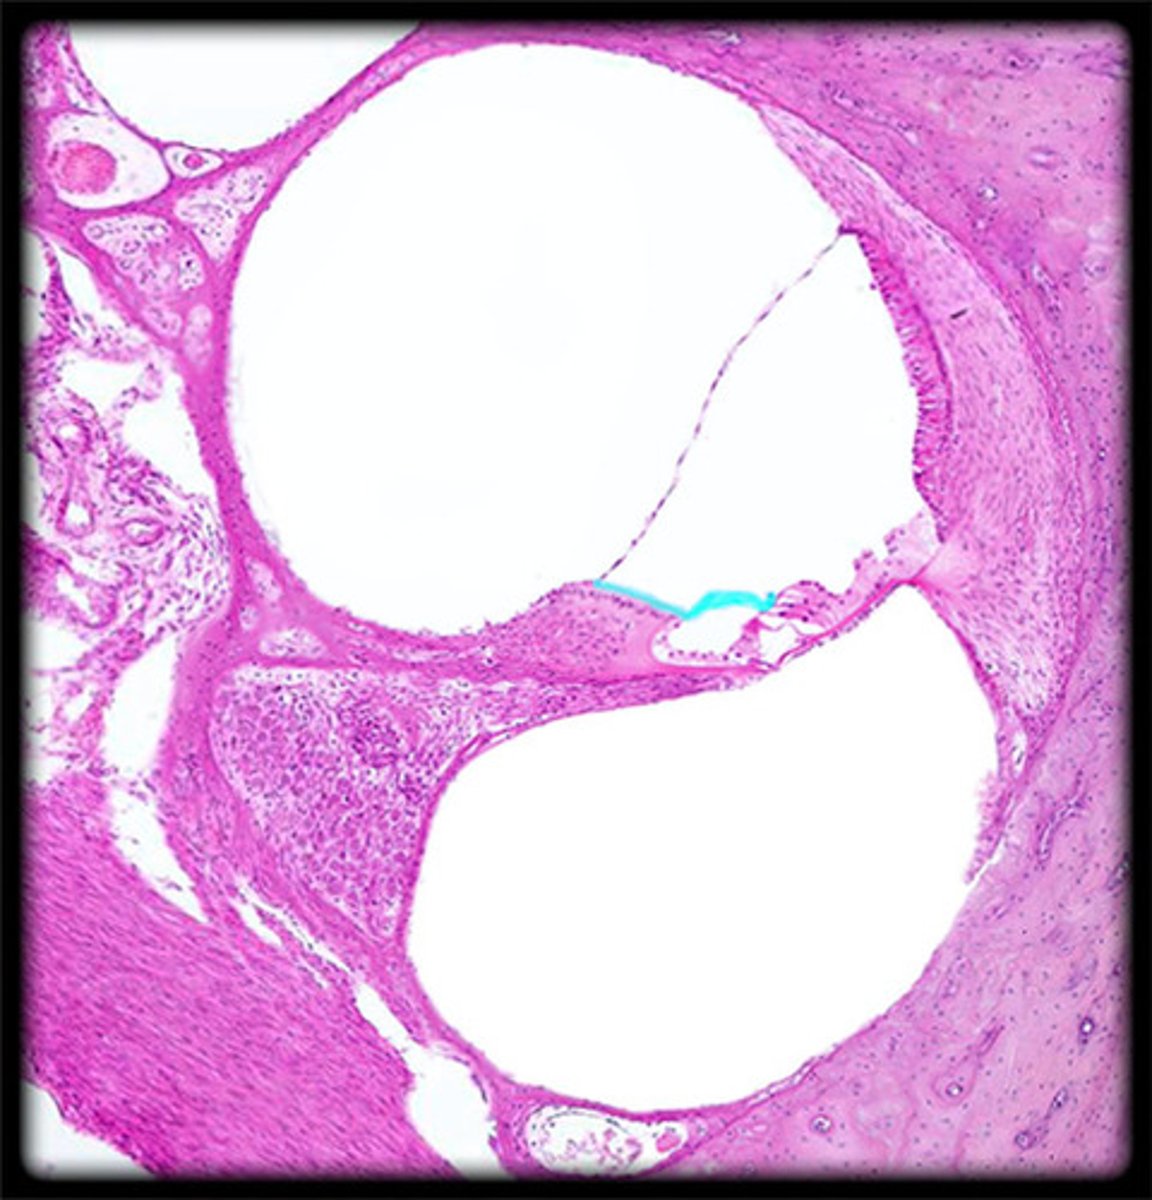

sclera histology

C

choroid histology

B

retina histology

A

ciliary body histology

E

posterior compartment histology

H

anterior compartment histology

Black dashed line

posterior chamber histology

F

anterior chamber histology

iris histology

D

lens histology

G

cornea histology

conjunctiva histology

ciliary process histology